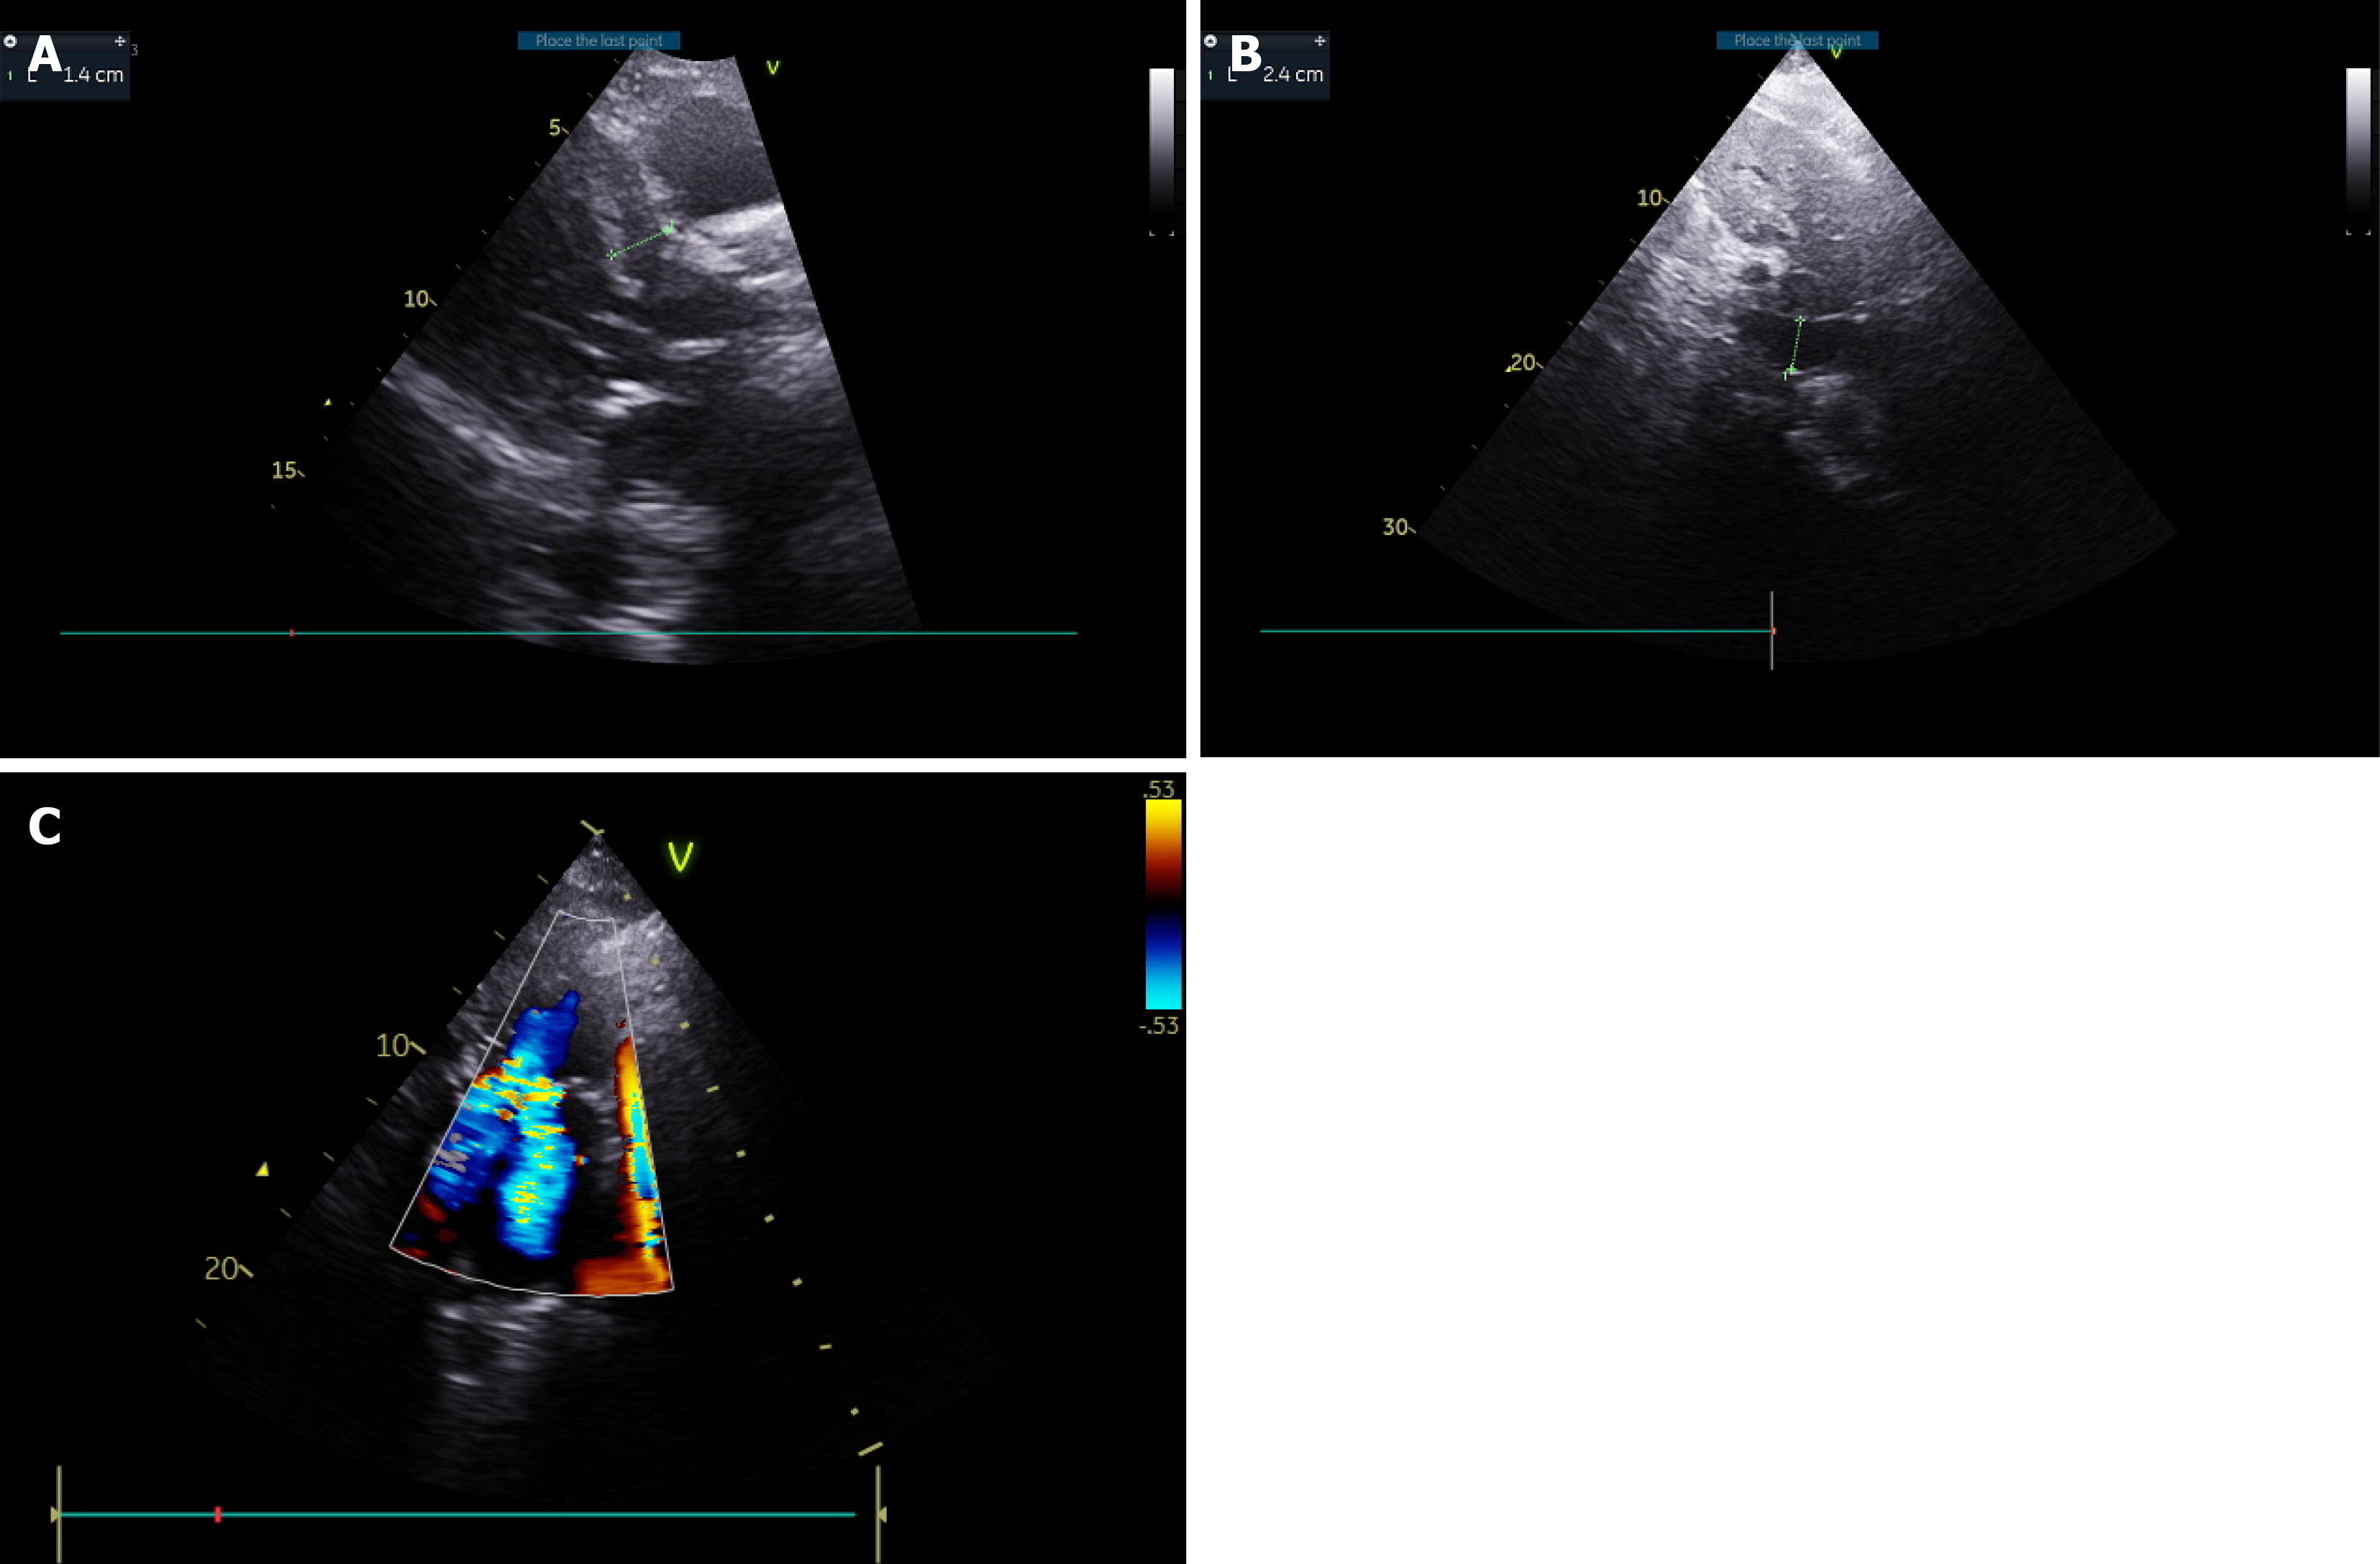

Figure 3 Hypertrophic left ventricle.

A: Interventricular septum dimension in end-diastole = 1.4 cm; B: Plethoric inferior vena cava; C: Systolic anterior motion of mitral valve with severe mitral regurgitation and left ventricular outflow tract obstruction.